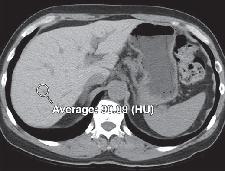

肝脏正常密度是多少?(悄悄告诉你,45HU-65HU)。遇到肝脏密度弥漫增高的患者,我们诊断思路是什么,考虑哪些疾病?该如何鉴别诊断?

CT:肝脏密度弥漫性增CT值达75HU-130HU,肝内血管密度相对减低(又称为“白肝病”);

平扫CT肝脏密度相对增高应考虑是否使用了抗心律失常药物胺碘酮。胺碘酮含有碘,胺碘酮的代谢产物脱乙基胺碘酮与肝脏亲和力大,在肝脏中积聚和代谢,导致肝脏密度增加。确切的由胺碘酮所致肝毒性相对罕见。

CT:肝脏密度均匀性增高;